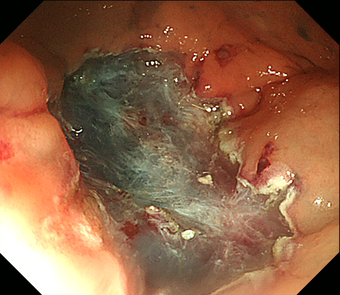

3)内視鏡的粘膜下層剥離術(ESD)

2cmを越える大きな腫瘍では、通常の内視鏡的ポリープ切除や粘膜切除術では一度に切除することが難しくなります。何度かに分割して切除すると再発率が高いため、内視鏡的粘膜下層剥離術(ESD)で腫瘍全体を一度に切除する方法を行います。ESDではヒアルロン酸溶液などを粘膜下に注入し病変を盛り上げてから、ナイフで少しずつ病変を削り取って切除します。現在のところ大腸がんに対するESD は高度先進医療実施施設でのみ実施が可能です。大きな潰瘍ができるため出血や穿孔の危険性が高くなるため、通常1週間くらいの入院が必要です。